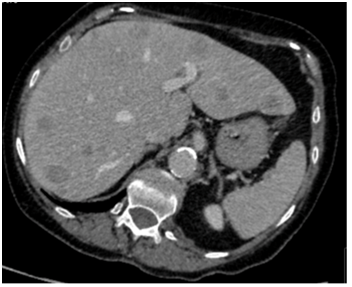

Our patient was a 79-year old female with severe progressive chronic obstructive pulmonary disease (COPD) on home oxygen, type 2 diabetes, hypertension and angina. She presented with type 1 respiratory failure and chest pain in December 2015. A computed tomography pulmonary angiogram (CTPA)4 months prior to this admission, showed no pulmonary embolism but did show a solitary liver lesion (Figure 1), measuring 2.5cm x 2.8cm that was suspicious for metastasis. A subsequent contrast-enhanced staging CT abdomen and pelvis demonstrated multiple liver metastases (Figure 2) with a 5.5cm solid-cystic lesion arising from her left kidney. After discussion with the Hepatobiliary multidisciplinary team (MDT), she underwent a percutaneous biopsy of the liver lesions, which showed metastatic carcinoma of indeterminate primary. She was seen by our Oncologists and was deemed suitable only for palliative treatment at this stage due to a presumed metastatic renal cancer and her multiple co-morbidities.

Figure 2: Staging CT chest abdomen and pelvis showing multiple liver metastases in December 2015.